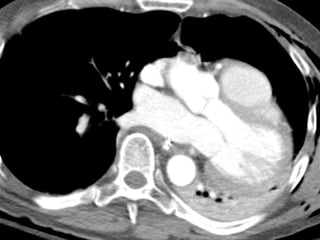

Blunt Cardiac Injury Myocardial Rupture

Blunt Cardiac Injury Cardiac Luxation